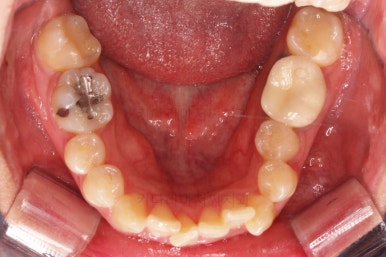

초진 시 입안의 모습입니다.

전반적으로 치열이 삐뚤고, 특정 앞니는 톡 튀어나가 미적으로 좋지 못한 상황이었습니다.

이갈이, 이악물기 습관도 있어서 앞니는 삐뚤어진 채로 치아가 많이 갈려있는 상황이었습니다.